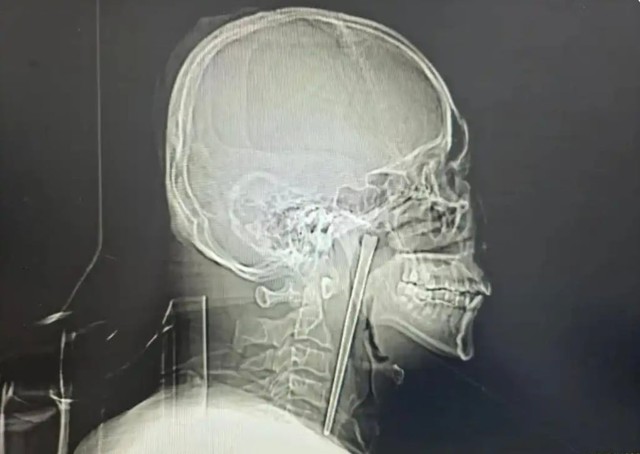

Một người đàn ông họ Vương tại Trung Quốc vừa trở thành tâm điểm chú ý trên mạng xã hội sau khi các bác sĩ phát hiện và lấy ra một chiếc đũa kim loại dài 12 cm đã nằm trong cổ họng ông suốt 8 năm. Câu chuyện không chỉ khiến nhiều người kinh ngạc mà còn đặt ra những câu hỏi về nhận thức sức khỏe và tâm lý sợ hãi phẫu thuật của bệnh nhân.

Trước việc bệnh nhân tiếp tục từ chối phương án rạch cổ, các bác sĩ đã lựa chọn một giải pháp khác ít xâm lấn hơn, đó là tiến hành phẫu thuật qua đường miệng. Ca mổ được thực hiện cẩn thận và thành công khi chiếc đũa kim loại dài 12 cm được lấy ra mà chỉ gây chảy máu ở mức tối thiểu.